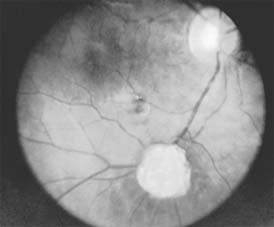

Astrocytic (Glial) Hamartomas

Astrocytic hamartomas are translucent to whitish retinal and optic nerve head tumors most frequently associated with tuberous sclerosis (Bourneville's disease) (Figure 10-31). They may also be associated with neurofibromatosis-1 and -2 or may occur as isolated findings. These tumors are congenital. They may grow slowly and, as they mature, become calcified, acquiring a mulberry configuration.

Figure 10-31

Figure 10-31: Retinal astrocytic hamartoma.